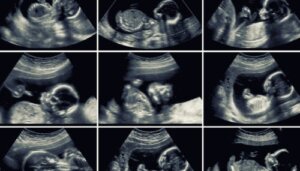

Misdannelsesscanning omkring uge 20 er en rutineundersøgelse, der giver mulighed for en grundig vurdering af barnets organer, moderens livmoder og moderkagen. Ud over de værdifulde oplysninger, den giver, udføres den på et vigtigt tidspunkt i graviditeten.

Generelt er denne ultralydsundersøgelse 2D. Hvis apparatet tillader det, kan nogle billeder dog optages i 3D eller 4D. Sidstnævnte viser barnets ansigtstræk med større præcision og viser endda dets bevægelser i realtid.

Specialisten kan kombinere 2D- og 3D-billeder for at få en mere komplet analyse af alle barnets strukturer.